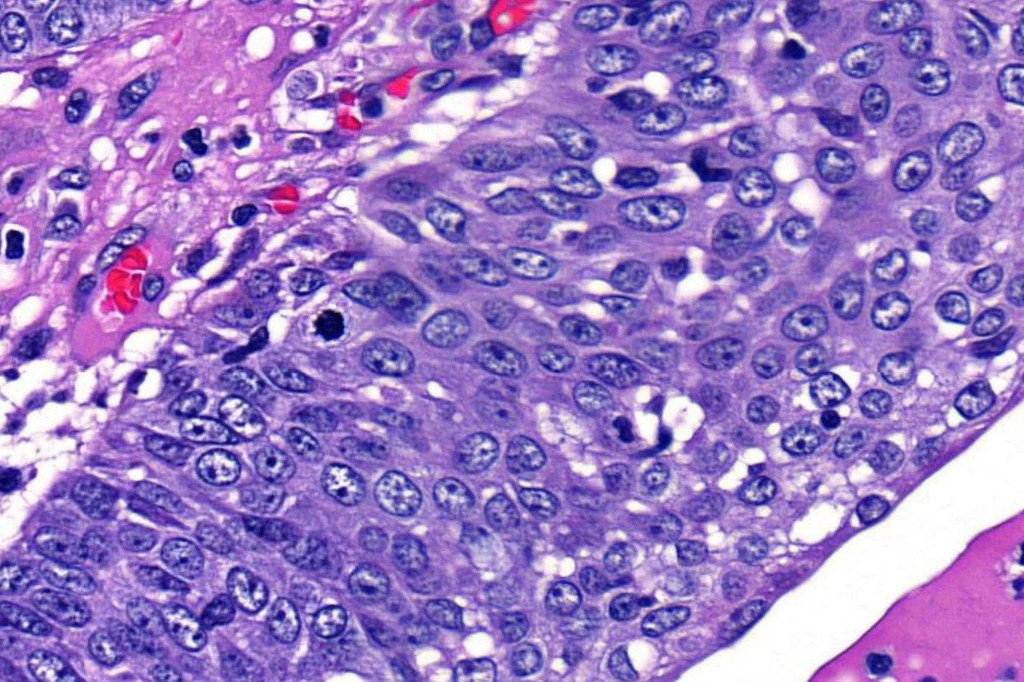

•Well differentiated lobular growth pattern though to a poorly differentiated tumor often showing a diffuse, infiltrating border which may extend into the subcutaneous fat

•Peripheral palisading with retraction artifact and mucin deposition as seen in basal cell carcinoma is not present

•Tumors are composed of an admixture of darkly staining basaloid cells with hyperchromatic or vesicular nuclei and more obvious sebaceous cells with eosinophilic, bubbly, multivacuolated cytoplasm frequently indenting the nucleus (scalloped)

•Often mitoses are numerous and abnormal forms evident

•Variable Lymphovascular invasion & perineural infiltration

Sebaceous carcinoma from a patient with Muir-Torre syndrome kindly shared by Dr. Antonina Kalmykova.